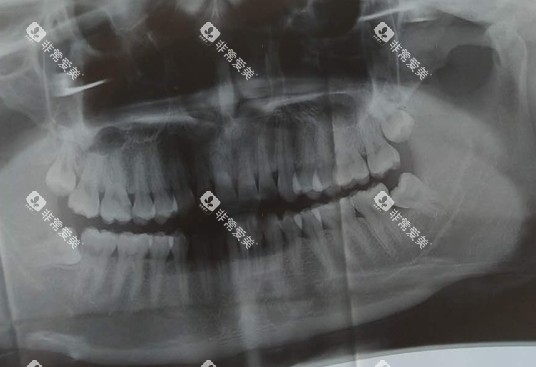

拔智齿是很多人都经历过或者可能会面临的牙科项目。

在金华地区,拔智齿的收费价格大致在 300 - 1000 元。

不过,这个价格并不是固定不变的,它受到多种因素的影响。

智齿的生长位置是影响价格的重要因素之一。

如果智齿生长位置比较正,拔除相对容易,医生操作起来也较为简单,那么收费可能就会接近 300 元这个低价。

但要是智齿是阻生智齿,比如水平阻生、倒置阻生等,拔除难度就会大大增加。

医生需要花费更多的时间和精力,可能还需要借助一些特殊的工具和技术,这种情况下收费就会偏高,接近 1000 元甚至更高。

此外,医院的级别和医生的经验也会对价格产生影响。

一般来说,大型的综合医院设备更较高,医生的技术也更有维持,但收费可能会比一些小型诊所高一些。

而经验充足的医生由于其正规技能和临床经验,收取的费用也可能相对较高。